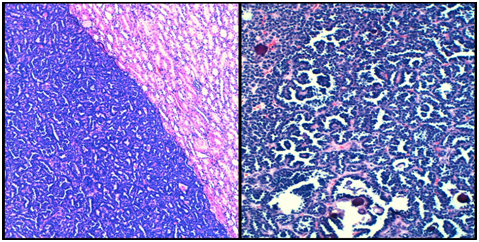

During the specimen sampling another solid nodular well- defined lesion was observed, located in the upper pole; a 0.8 cm diameter tumor with similar macroscopic features to those described in the former nodule. Furthermore, two renal retention cysts were found (measuring 3 and 1 cm diameter). Histologically, both solid tumors were composed of a highly cellular neoplasm (Figure 1) with basophilic proliferation of small rounded and extremely uniform cells with smooth nuclear contours, scant pale cytoplasm, dark-staining nuclei, and inconspicuous nucleoli. These tumoral cells were arranged into compact ductal and acinic fashion, with glomeruloid and papillary structures. Several psammoma bodies were also identified (Figure 1). Mitotic figures were absent throughout the lesion. The tumor expressed CK AE1AE3, CK18 and Vimentin (Figure 2). Besides, it was EMA, CK7 and WT-1 negative. The final diagnosis was MA.

Figure 1 Well-defined and highly cellular neoplasm (left, HEx100). Several psammoma bodies and papillary structures were identified (right, HEx200).